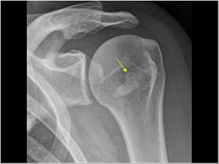

رادیوگرافی می توان تندینیتس و رسوب کلسیم در تندون را نشان بدهد، علاوه بر این دو مورد رادیوگرافی می تواند شکستگی های استخوان کتف، ترقوه و بازو را نشان دهد. درد این شکستگی ها ممکن است با درد سندروم های درد شانه اشتباه گرفته شود. درصورت شک پزشک به پارگی تندون های شانه MRI و تصویربرداری سونوگرافی انجام می شوند. بر اساس شرح حال بیمار و تشخیص بیمار ممکن است نیاز به انجام آزمایشات دیگری مانند شمارش کامل سلول های خونی باشد.

تصویر رادیوگرافی: